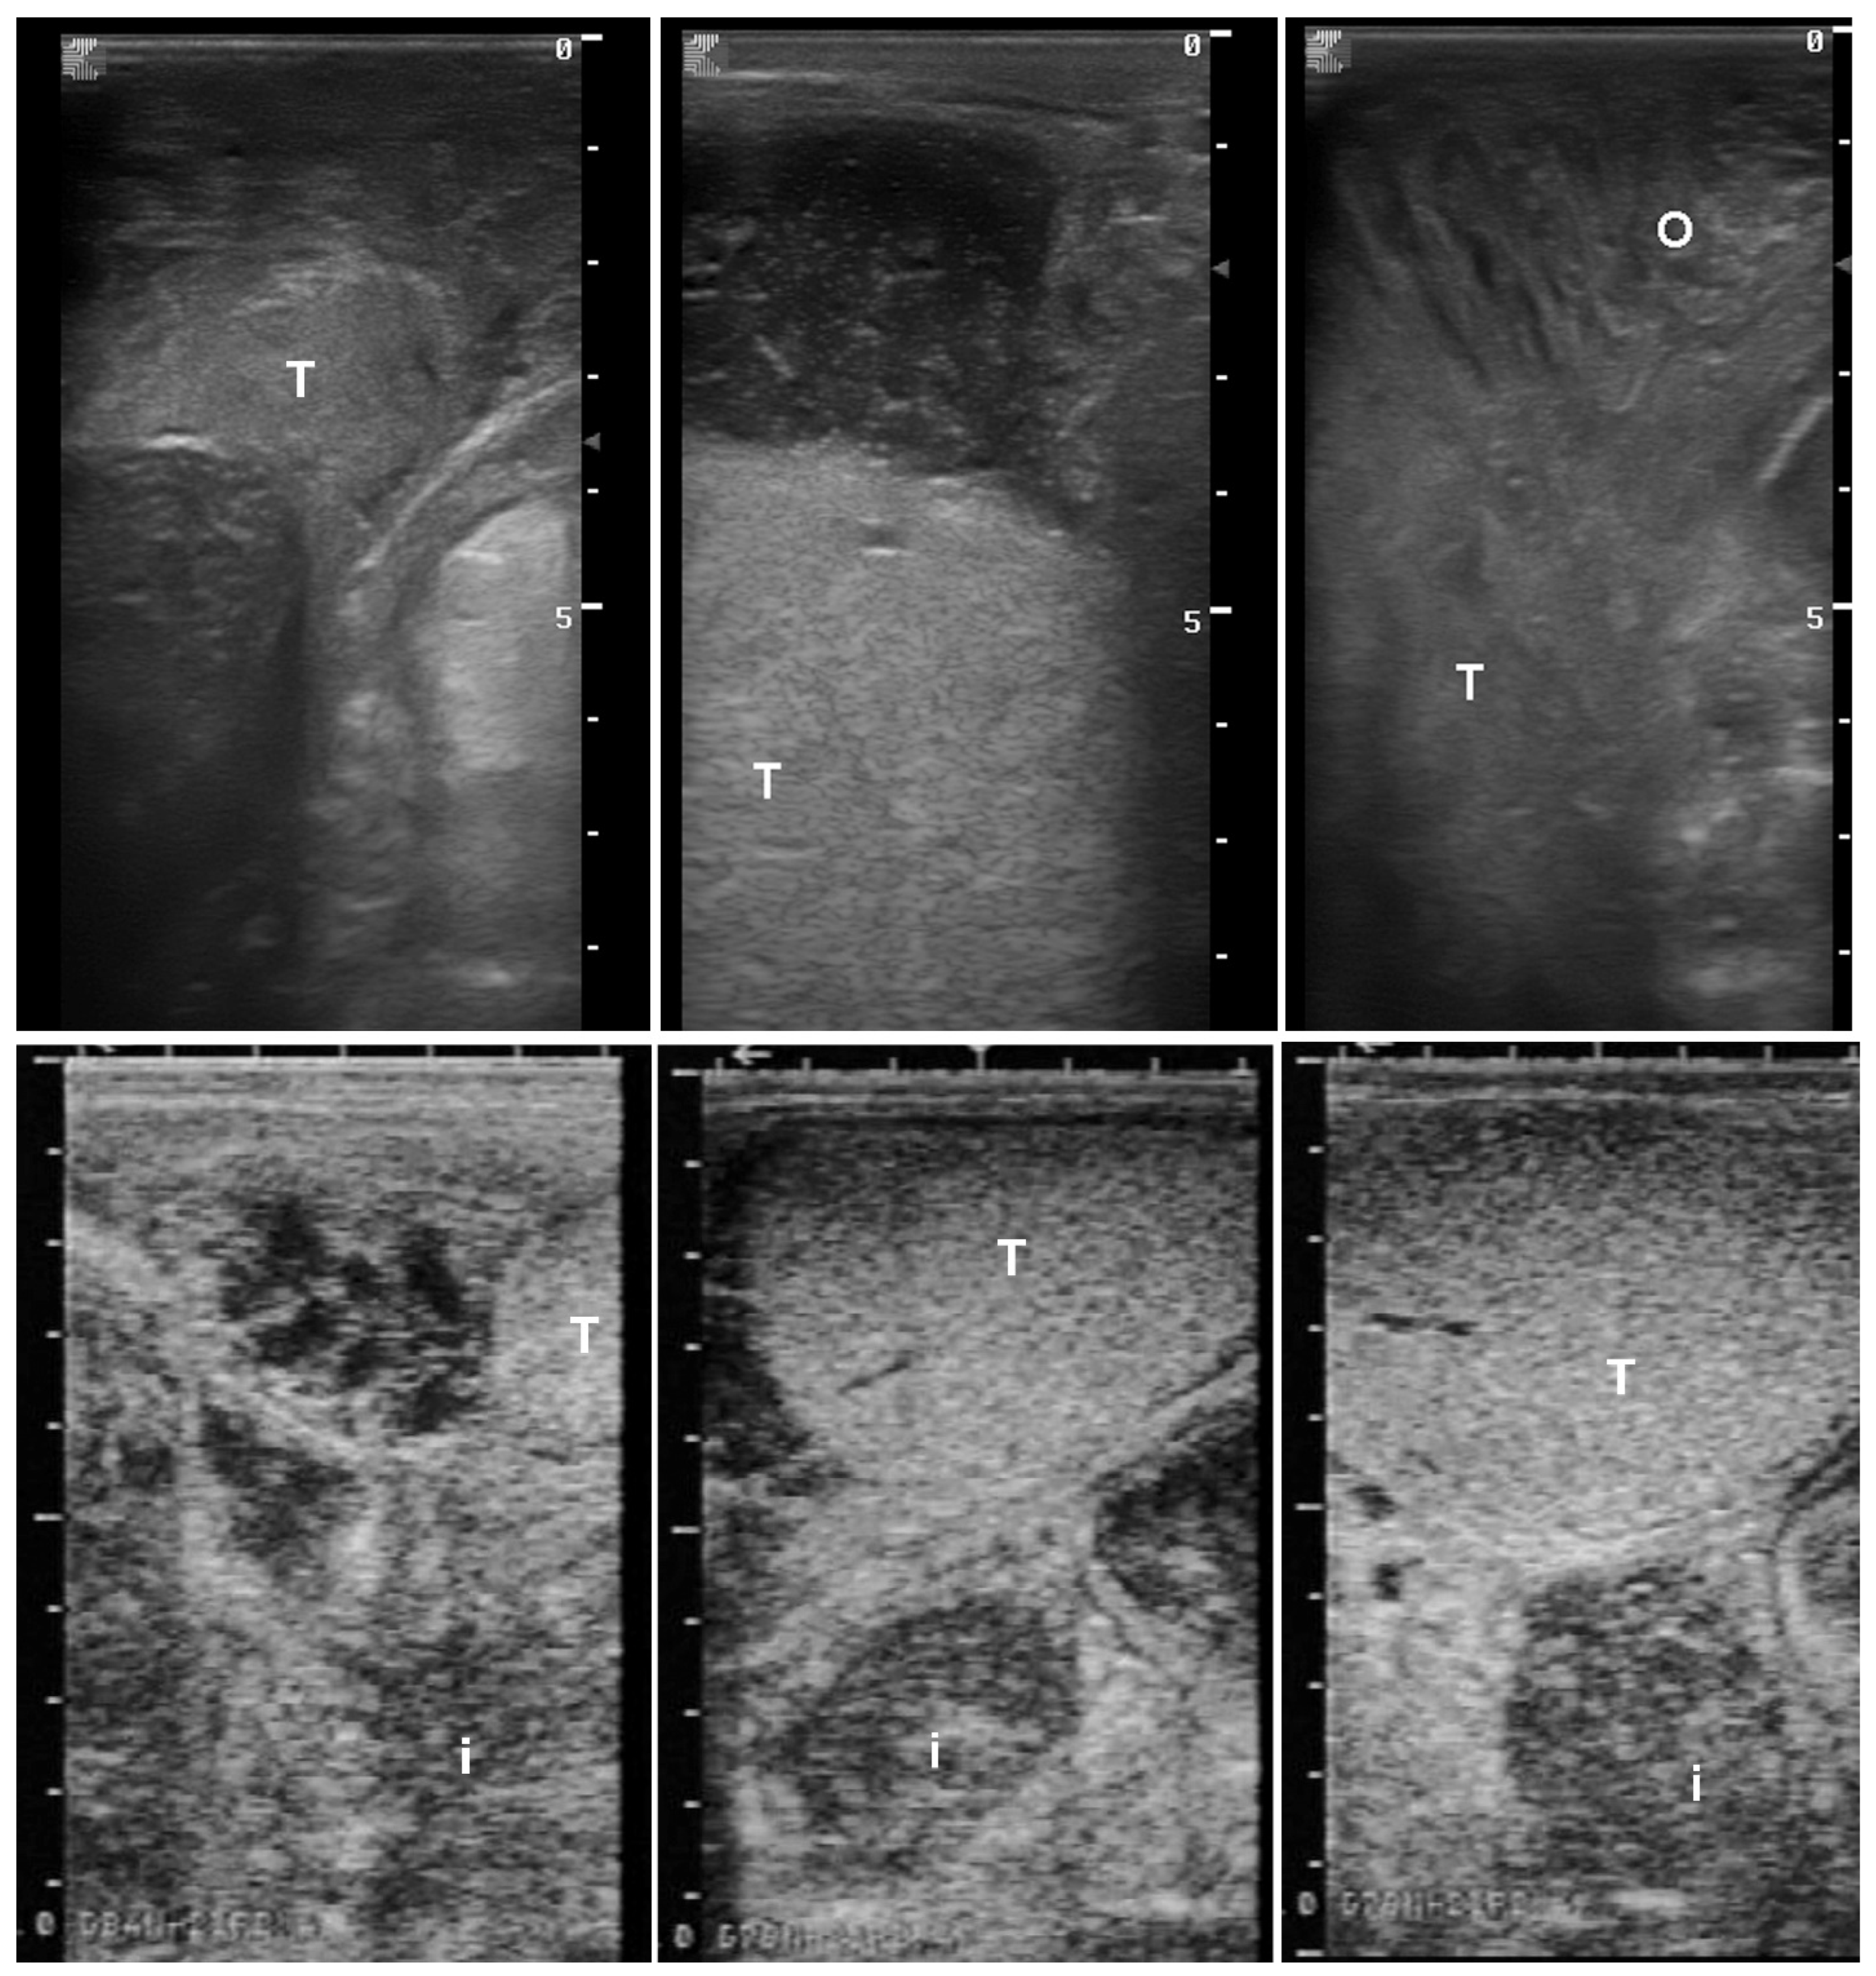

6. Asymmetric Testis/Testicular Degeneration